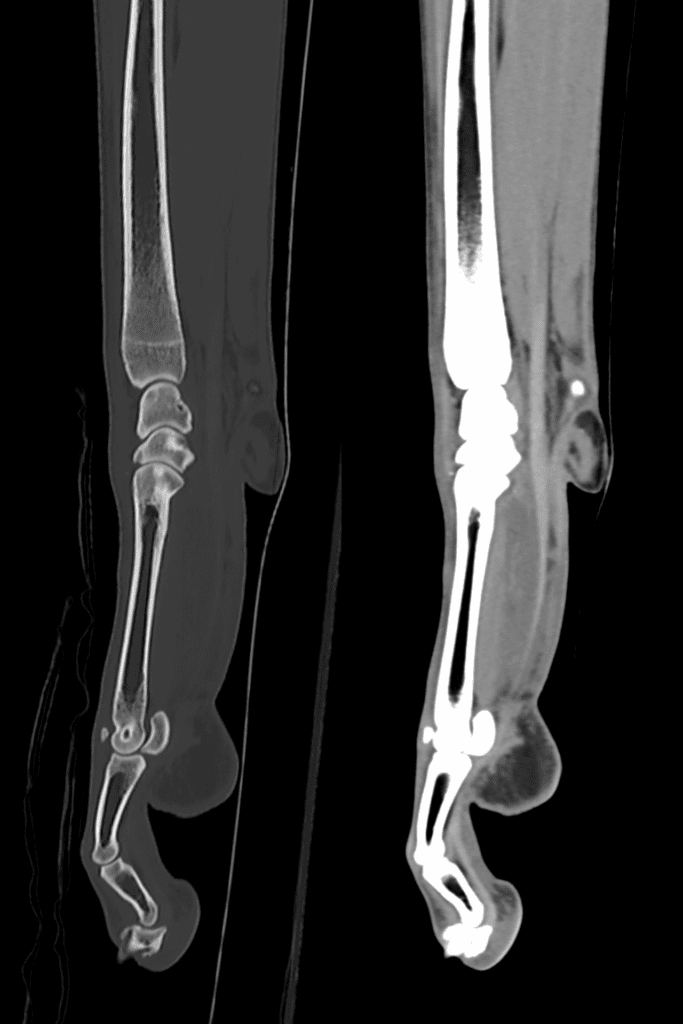

Nico’s CT scan for his carpal (wrist) laxity

Nico the wonderful wolfhound was struggling to weight bear on his right carpus and his neurologist mum Nadia Shihab brought him to see our orthopaedic team.

A physical examination showed carpal laxity on the right carpus so his orthopaedic surgeon immediately referred Nico for a CT scan using our 160-slice CT scanner to help him work out exactly what was happening in that joint. The high-resolution CT images were obtained in seconds, offering superior resolution of the bony anatomy, identifying small and subtle pathology and allowing 3D reconstruction of Nico’s carpus.

The diagnosis was progressive carpal collapse and treatment options included a pan carpal arthrodesis using a custom implant designed and modelled from the CT images so that it could fit Nico’s bones perfectly.